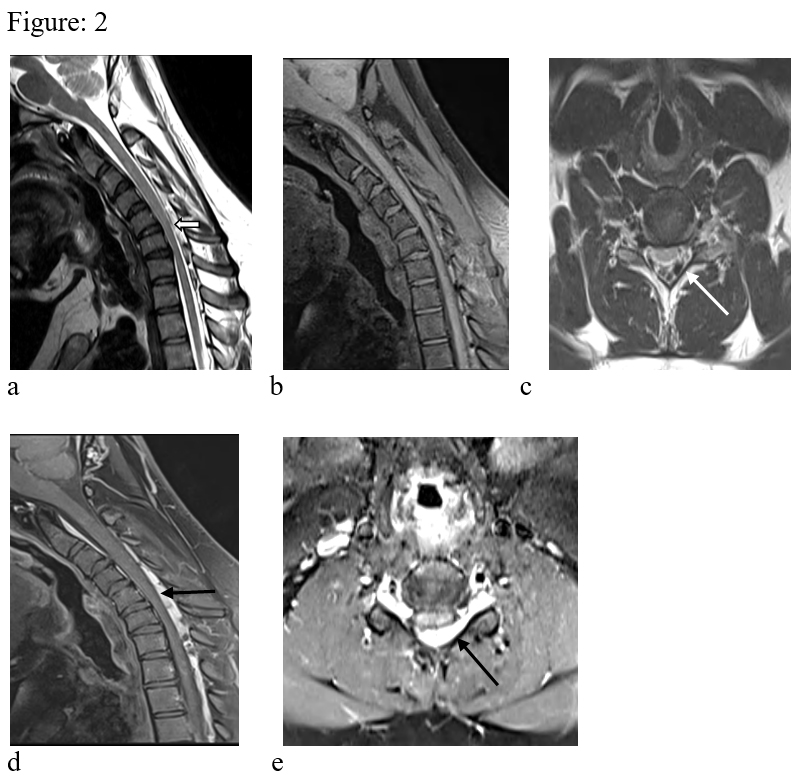

Figure: 2. T1 & T2 weighted images in flexion in sagittal (a, b) & axial (c) reveals anterior displacement of the dura (white block arrow) causing compression of the cervical cord. There is widening of the spino-dural space with prominent epidural veins (white arrow). The cervical cord shows atrophy. Sagittal & axial post contrast images in flexion (d, e) shows thick heterogeneously enhancing component in the epidural space (black arrow). There is also extension of the enhancing epidural lesion to the upper dosral region.